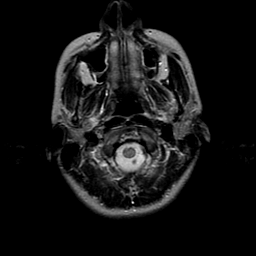

overlay -- Slice #0

[Home][Help][Clinical] Slice 0